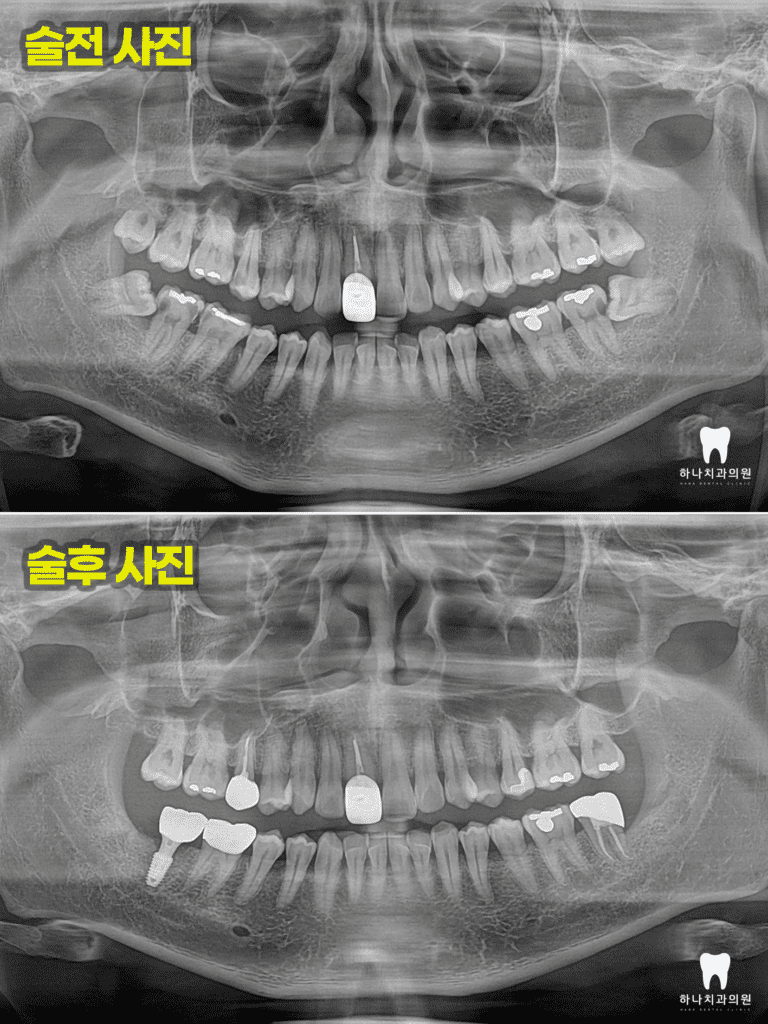

위 환자분께서는 30대 남성분으로

울산삼산동치과에 내원하셔서

진료받으신 경험이 있으신 배우자분의

추천으로 내원해 주셨는데요.

양쪽 어금니가 너무 아프고, 씹지도 못하신다며

치과가 무서워서 어렸을 때 말고는

와보신 경험이 없다고 말씀해 주셨습니다.

양쪽 아래 수평으로 매복되어 있는

사랑니가 관리되지 않아

바로 앞의 큰 어금니 뒤쪽으로

큰 우식을 공통적으로 가지고 있는

모습을 확인할 수 있었는데요.

오른쪽의 경우, 앞쪽에도 우식이

많이 진행된 상태였습니다.

따라서 양쪽에 매복되어 있는 사랑니를

발치하는데 심한 우식이 진행된 오른쪽의 경우

발치 후 임플란트, 왼쪽의 경우는 자연치 크라운을

진행하시기로 계획을 수립하였습니다.

더불어 증상을 보이는 왼쪽 아래

가장 안쪽 어금니는 신경치료와 크라운,

양쪽 위 두 번째 작은 어금니 인접면의 우식은

진행이 심한 오른쪽의 경우 신경치료 및

포스트, 코어, 크라운을 진행하고

왼쪽의 경우 인레이 수복으로

계획을 하였습니다.